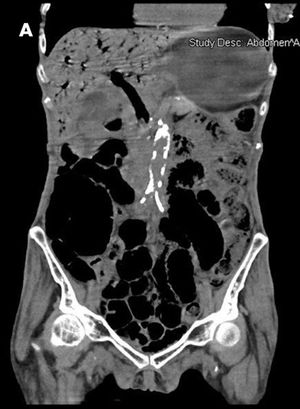

Pneumatosis IntestinalisByUmer Feroze Malik, MD,Usman Ali, MDOctober 6th 2009A 70-year-old woman with poorly controlled type 2 diabetes mellitus (hemoglobin A1c, 12.5%) and hypertension was brought to the emergency department for evaluation of abdominal pain and loose bowel movements.